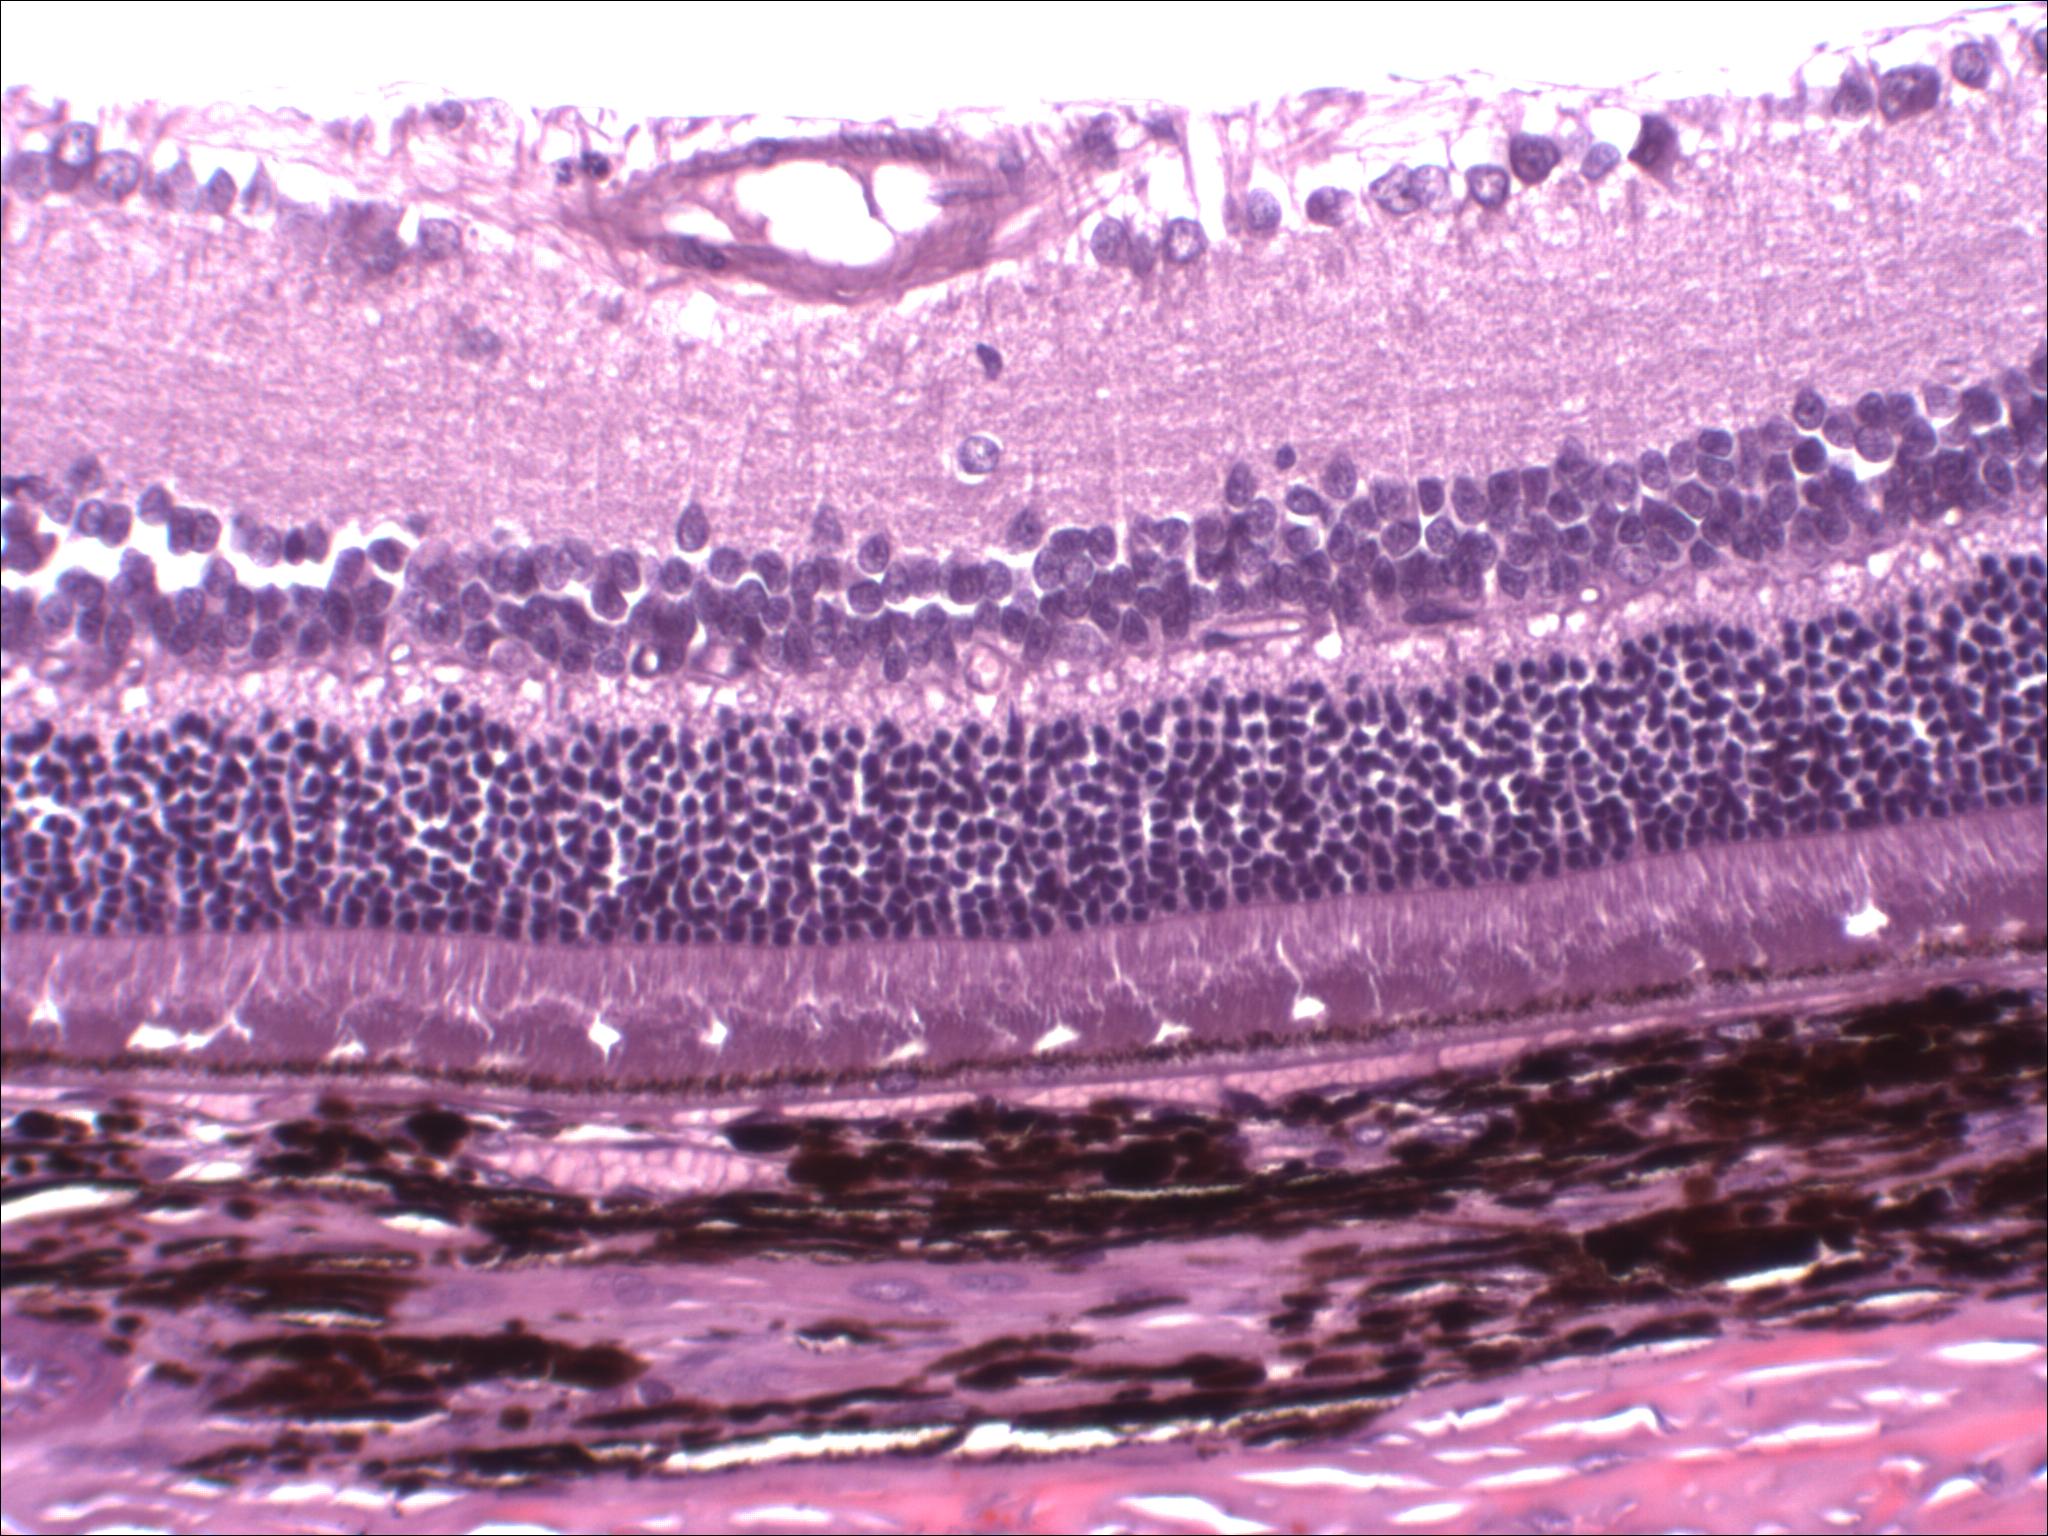

CBI offers a robust and validated model of STZ-induced hyperglycemia and retinopathy. Streptozotocin-induced hyperglycemia results in changes in the retinal pigmented layer consisting of increased thickness of the middle retinal layers, increased new vessel formation, reactive endothelium, dilated capillaries distended with either blood or edema fluid, acute inflammation composed of intravascular neutrophils, and neutrophils adhered to vessel walls and extravascularly by 4 weeks or longer post-STZ treatment. These changes were clearly evident histologically and were supported by Optical Coherence Tomography and retinal angiography. Examination of the retina via fluorescein angiographs reveals increases in retinal vascularity in streptozotocin-treated groups with areas of leakage particularly surrounding the optic nerve. These changes were compatible with and correlated with the histopathologic findings of increased vascularity of the retinal pigmented layer. OCT assessments clearly demonstrating thickening of the retina, primarily the middle layers following STZ induction. Treatment with triamcinolone significantly reduced STZ-induced retinal thickness as well as other ocular changes.